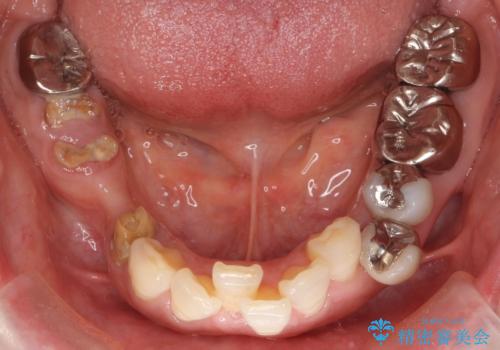

奥歯でしっかり咬むことができるようになり、大変喜んで頂けました。

クラウンの種類:オールセラミッククラウン ベレッツァ